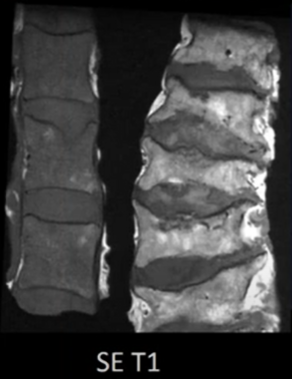

Moelle osseuse - quelques lésions focales